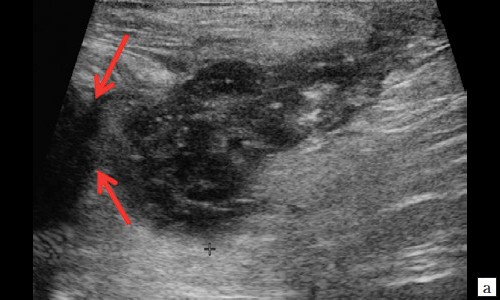

Описываемое образование прилежит к передне-боковой утолщенной стенке анального канала, нечетко от нее дифференцируется (см. рис. 1, а, б). По периферии образования – выраженная сосудистая реакция (см. рис. 1, в). По периферии образования ближе к ягодичной области – формирующийся свищевой ход размером 1,3×0,6×0,6 см (см. рис. 1, г).

Рис. 1. а, б – В-режим. В перианальной области слева на глубине 0,6 см от поверхности кожи определяется гипоэхогенное жидкостное образование с четкими неровными контурами с наличием неоднородного гиперэхогенного подвижного содержимого размером 3,9×2,1×1,9 см, объемом 8,24 мл с утолщенными до 0,3 см стенками. Описываемое образование прилежит к передне-боковой утолщенной до 1,0 см стенке анального канала, нечетко от нее дифференцируется (стрелки);

Рис. 2. а, б – В-режим. Через 3 дня после оперативного вмешательства. Описываемое гипоэхогенное жидкостное образование с четкими неровными контурами с наличием неоднородного гиперэхогенного подвижного содержимого уменьшилось в размере до 2,4×1,7×1,8 см, до объема 3,84 мл (стрелки);

Рис. 3. а, б – В-режим. Через 14 дней после оперативного вмешательства. Гипоэхогенное жидкостное образование с четкими неровными контурами в перианальной области уменьшилось в размерах до 1,1×0,6×0,8 см, объемом 0,29 мл (стрелки);